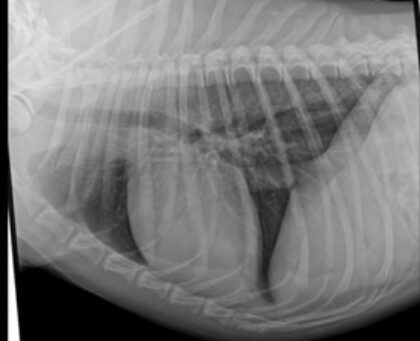

In diesem kompakten vetinar geht es um einen Einstieg in die systematische Beurteilung der nicht-knöchernen Strukturen im Thoraxröntgen – von Herz und Gefäßen über Pleura und Mediastinum bis hin zu verschiedenen Lungenzeichnungen.

Es werden einige typische Befunde und auch rassespezifische Besonderheiten gezeigt. Ideal zur kleinen Auffrischung oder als Grundlage für die Beurteilung in der Kleintierpraxis.